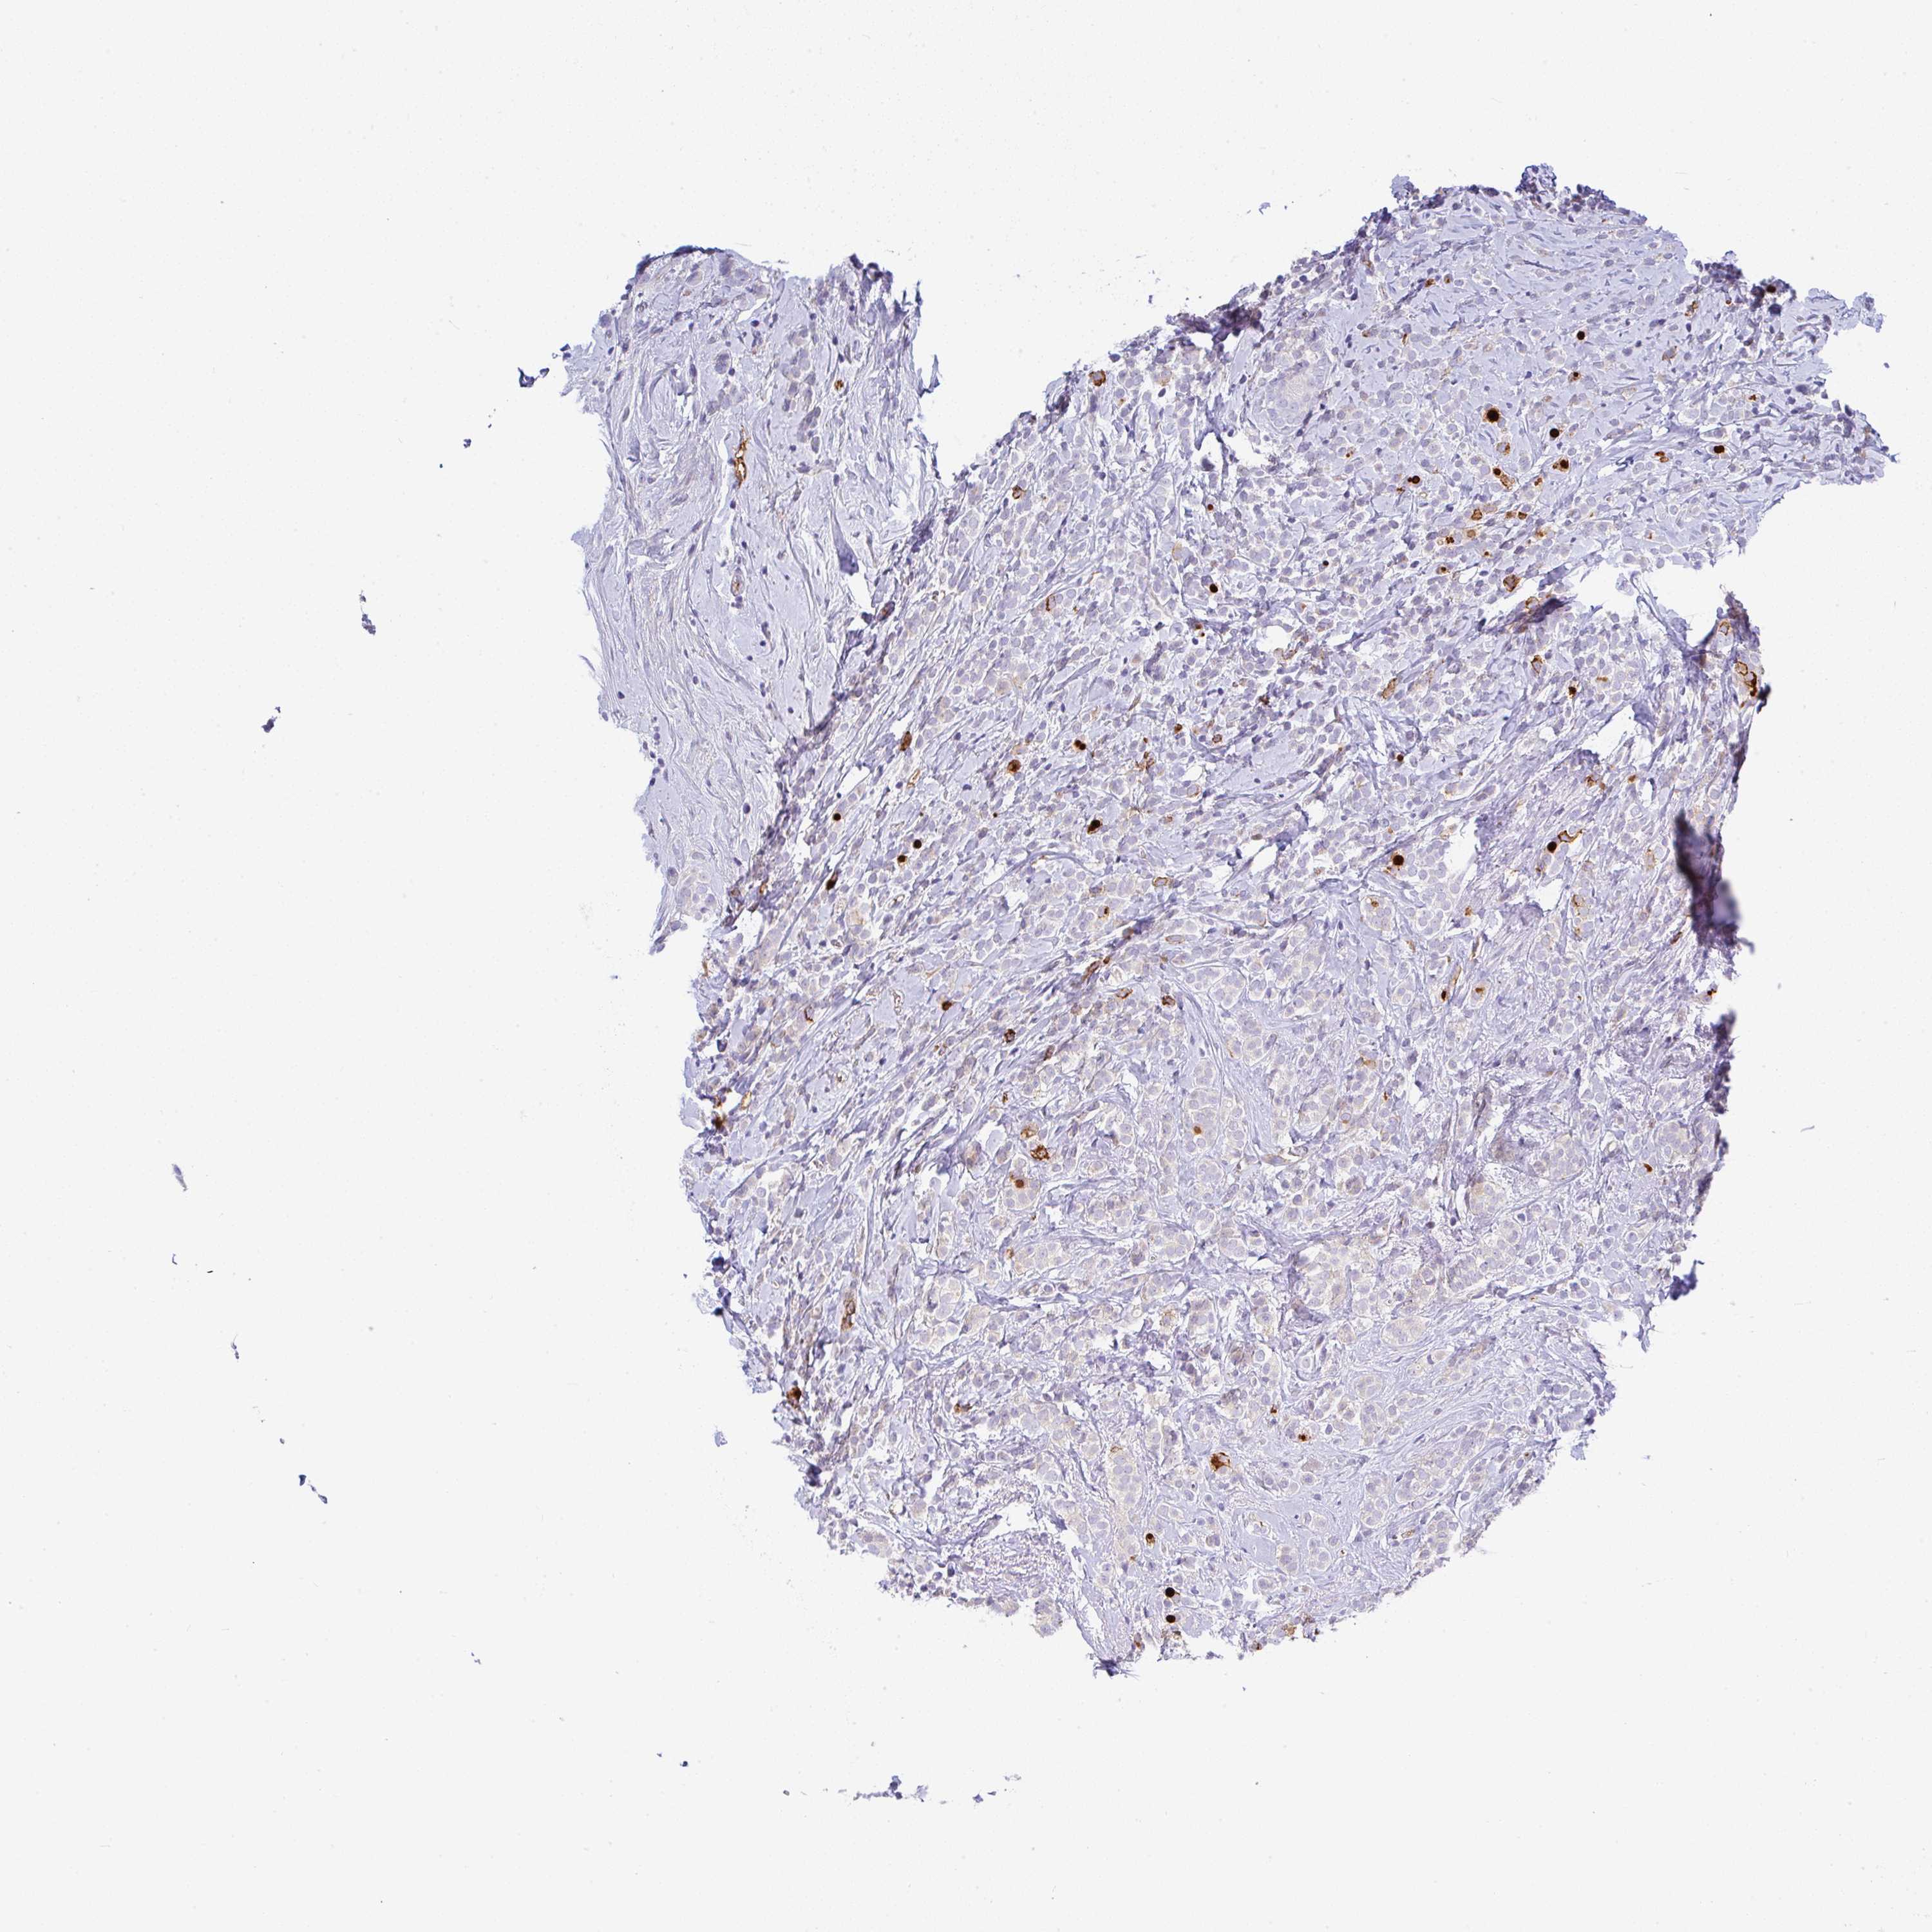

CANCER BREAST CANCER Show tissue menu

BRCA TCGA BRCA VALIDATION PROTEIN EXPRESSION

ANTIBODIES

AND

VALIDATION